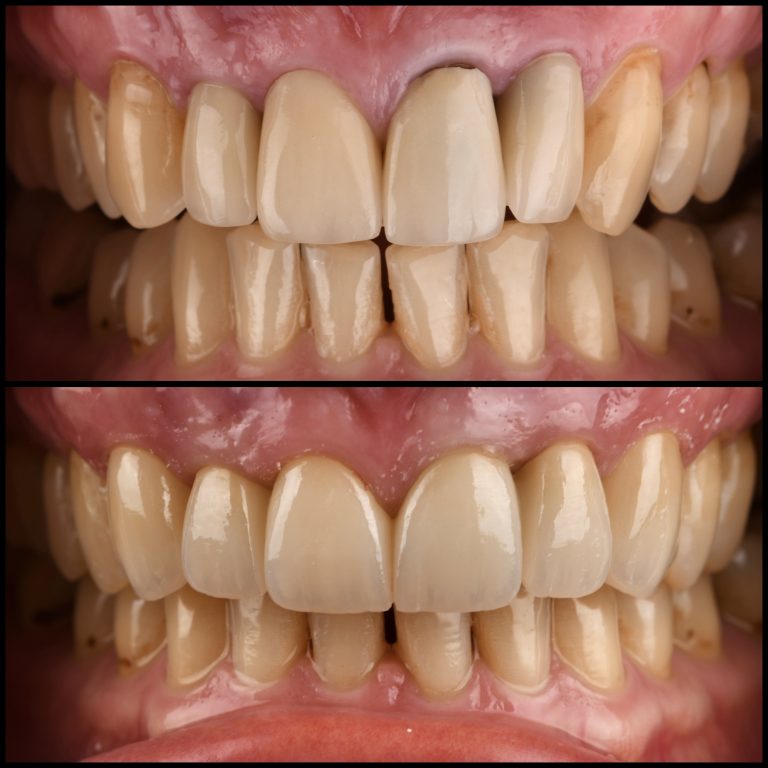

Keramičke fasete (ljuspice)

Fasete su veoma tanke keramičke nadoknade koje se lepe na prednju površinu zuba kako bi značajno poboljšale estetski izgled osmeha. Ova metoda je posebno popularna među osobama sa zdravim zubima koje žele vizuelnu transformaciju bez većih stomatoloških zahvata. Fasete omogućavaju prirodan izgled, a istovremeno ispravljaju razne nepravilnosti u boji, obliku, veličini ili položaju zuba. Osim što daju estetski savršen rezultat, fasete su izdržljive, dugotrajne i zahtevaju minimalno brušenje prirodnog zuba pre postavljanja.

Kada se preporučuju keramičke fasete:

• Za estetsko unapređenje osmeha

• Kod zuba nepravilnog položaja

• Kod okrnjenih ili istrošenih zuba

• Za zatvaranje razmaka između zuba